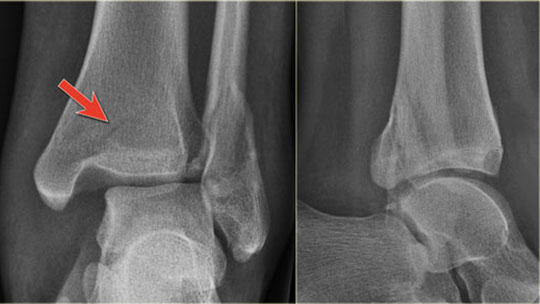

HOW IS AN ANKLE FRACTURE DIAGNOSED?

Ankle fractures generally require an

- X-ray

- MRI – If the doctor perceives tendon or ligament damage.

Your physician will use those x-rays or a MRI to check and see which bones are broken and which ligaments are damaged to decide on your treatment.